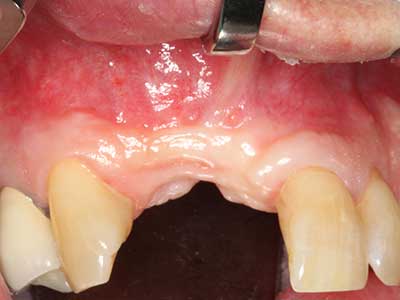

Marginal periodontal diseases are the main reason for extractions in advanced age. These diseases are primarily caused by bacterial colonization of the gingival pocket, which causes inflammation followed by loss of the periodontium. The formation of subgingival biofilms and concrements is a significant aetiological factor for marginal bone atrophy, so their removal is an important part of the treatment (Drisko 2014, Plessas 2014).

Initial and surgical treatment phases are differentiated in the treatment of marginal periodontitis. In addition to instruction in oral hygiene and motivating patients, both phases should include adequate cleaning of the root surface. In the regenerative setting an open access is generally preferred. The root surface can be cleaned by piezo surgery using special attachments, where instruments with different curvatures are used to reach areas that are difficult to access, such as furcations. The integrated irrigation in the system flushes the detached concrements and bacteria out of the pocket. Specialized systems such as the Piezomed also include application feedback to minimize the ablation of hard dental substance. The greater the pressure on the periodontal attachment the greater the reduction in the amount of ablation.